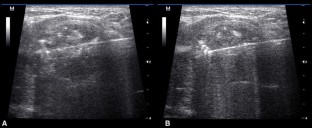

Fig. 1

Fig. 2

Fig. 3